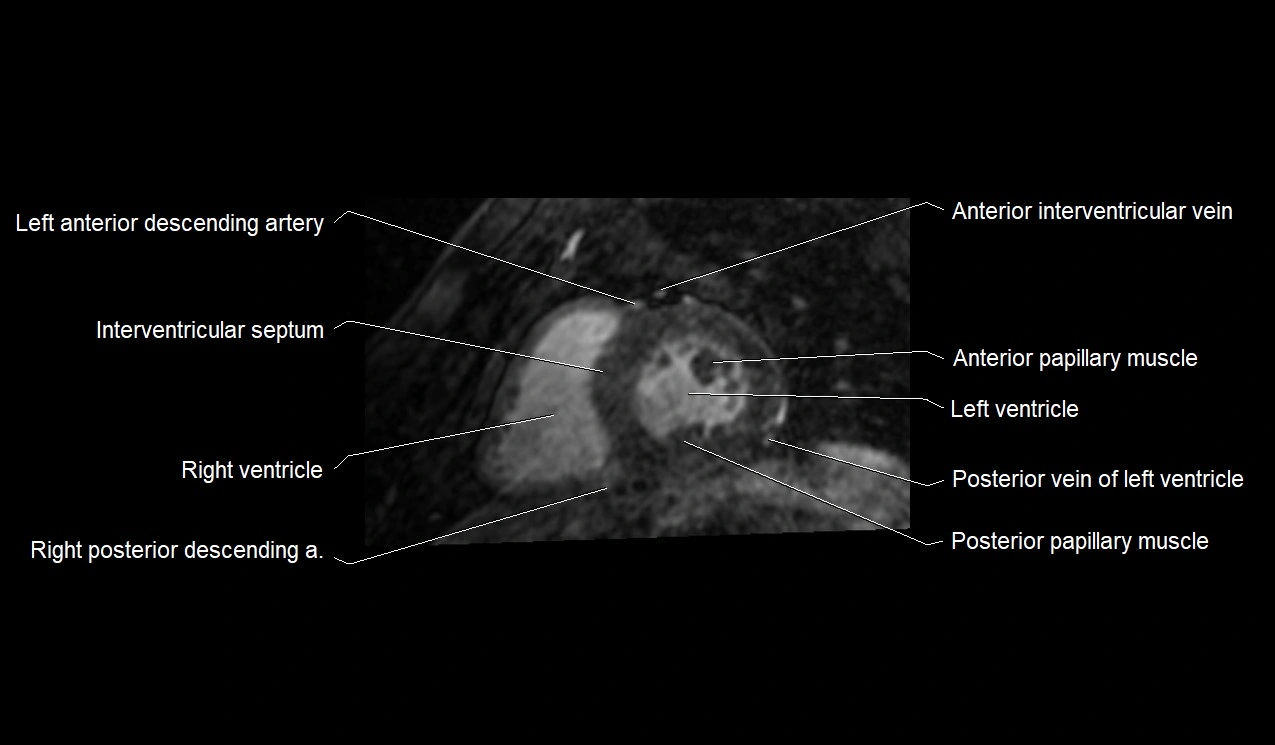

- Anterior papillary muscle

- Interventricular Septum

- Left ventricle

- Posterior papillary muscle

- Posterior vein of left ventricle

- Right posterior descending coronary artery (Right PDA)

- Left anterior descending artery (LAD)